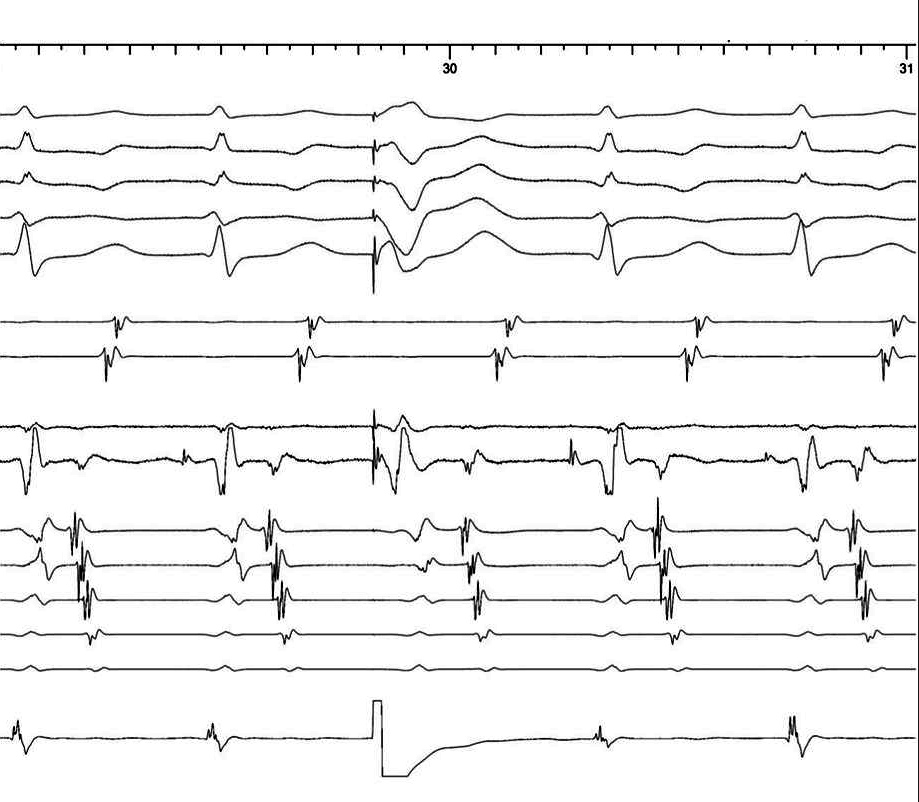

Sinus rhythm - Map catheter in anterior CS os

Fractionated signal

• Fractionated A from previous ablation

• AP potential

• His signal